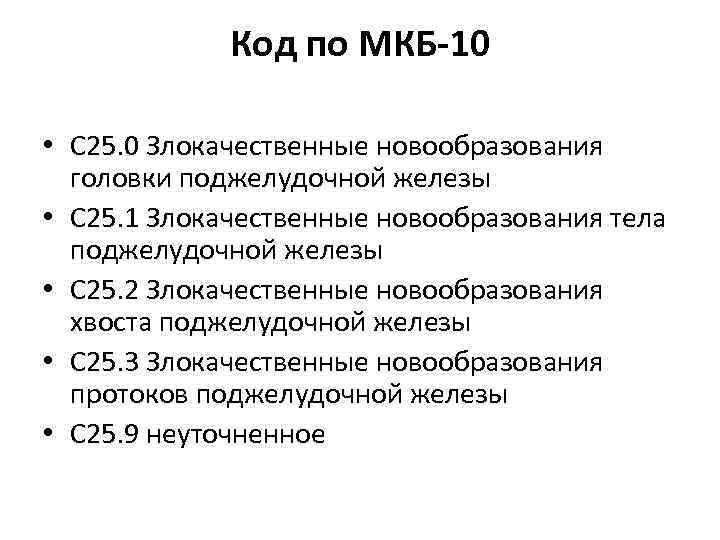

Код мкб 10 атерома головы

Код мкб 10 атерома головы 109 фото